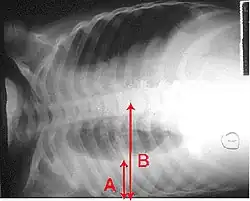

Zapalenie płuc diagnozowane jest zazwyczaj w oparciu o połączenie objawów fizycznych i rtg klatki piersiowej[35]. Trudno może być jednak potwierdzić główną przyczynę, ponieważ nie istnieje żaden test pozwalający definitywnie rozróżnić podłoże bakteryjne od niebakteryjnego[6][35]. Światowa Organizacja Zdrowia zdefiniowała zapalenie płuc u dzieci w oparciu o takie objawy kliniczne, jak kaszel lub trudności w oddychaniu i przyspieszony oddech, zapadnięta klatka piersiowa lub obniżony poziom świadomości[36]. Przyspieszony oddech definiowany jest jako więcej niż 60 oddechów na minutę u dzieci w wieku poniżej 2 miesięcy, 50 oddechów na minutę u dzieci w wieku od 2 miesięcy do 1 roku lub ponad 40 oddechów na minutę u dzieci w wieku od 1 roku do 5 lat[36]. U dzieci przyspieszone tempo oddechu i zapadnięta dolna część klatki piersiowej wykazują większą czułość niż wysłuchanie rzężeń w klatce piersiowej za pomocą stetoskopu[10].

W diagnozie często wykorzystuje się zdjęcie rentgenowskie klatki piersiowej[10]. W łagodnych postaciach choroby obrazowanie konieczne jest tylko w razie potencjalnych powikłań, niejasnej przyczyny choroby oraz u osób, których stan nie uległ poprawie mimo leczenia[10][37]. Prześwietlenie zalecane jest u osób w stanie na tyle poważnym, że wymagają hospitalizacji[37]. Wyniki jednak nie zawsze korelują ze stadium zaawansowania choroby i nie pozwalają na wiarygodne rozróżnienie pomiędzy infekcją o podłożu bakteryjnym a wirusowym[10].

Obrazy RTG zapalenia płuc można sklasyfikować jako przedstawiające płatowe zapalenie płuc, oskrzelowe zapalenie płuc (znane również jako zrazikowe zapalenie płuc) oraz śródmiąższowe zapalenie płuc[40]. Bakteryjne, pozaszpitalne zapalenie płuc w postaci klasycznej wykazuje konsolidację jednego segmentarnego płata płuca i znane jest jako płatowe zapalenie płuc[20]. Wyniki mogą jednak się różnić, a w innych typach zapalenia płuc powszechne są inne wzory zmian[20]. W aspiracyjnym zapaleniu płuc obraz może wykazywać dwustronną nieprzezroczystość głównie u podstawy płuc i po prawej stronie[20]. Obrazy wirusowego zapalenia płuc mogą wydawać się normalne, płuca nadmiernie rozdęte, z dwustronnymi niejednolitymi obszarami lub podobne do bakteryjnego zapalenia płuc z konsolidacją płata[20]. Zmiany mogą nie być widoczne w obrazach RTG we wczesnych stadiach choroby, zwłaszcza w wypadku odwodnienia; mogą być również trudne do zinterpretowania u osób otyłych lub z historią chorób płuc[11]. W ostatnich latach istotne badania kliniczne wykazały, że ultrasonografia klatki piersiowej, wykonywana przez doświadczonych specjalistów, charakteryzuje się dokładnością diagnostyczną równą, a nawet przewyższającą radiografię klatki piersiowej w diagnostyce zapalenia płuc. Podejście to znajduje coraz szersze zastosowanie w praktyce klinicznej[41]. W trudnych do określenia przypadkach dodatkowe informacje można uzyskać dzięki tomografii komputerowej[20].